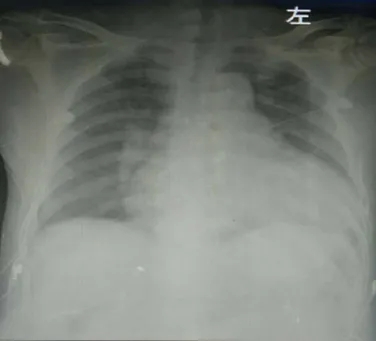

胸片(入院当天):心影明显增大